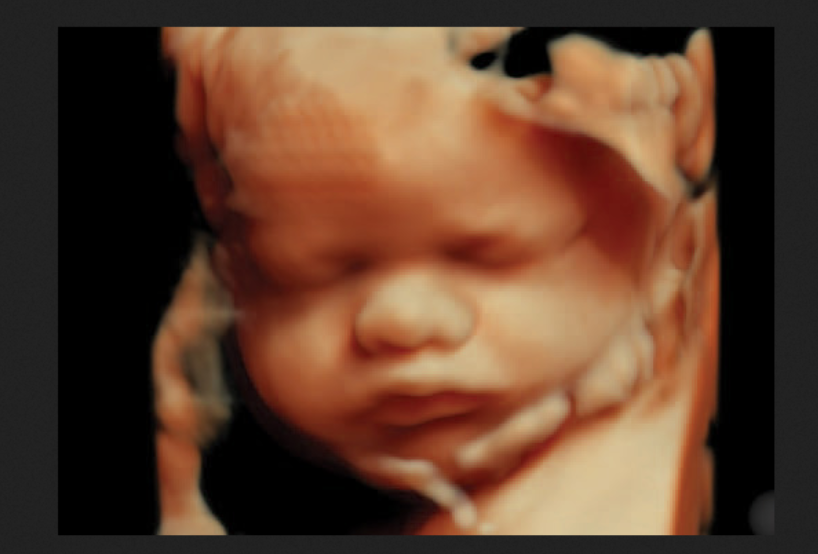

La ley de aborto del Reino Unido está perjudicando tanto a las mujeres como a los bebés no nacidos. Es una tragedia nacional que se hayan perdido 11.105.671 vidas desde que entró en vigor la Ley de Aborto de 1967; cada una de ellas era un ser humano único y valioso al que se le negó el derecho a la vida”.

“Cada una de estas vidas era la de un hijo o una hija, y cada una de estas vidas importaba”.